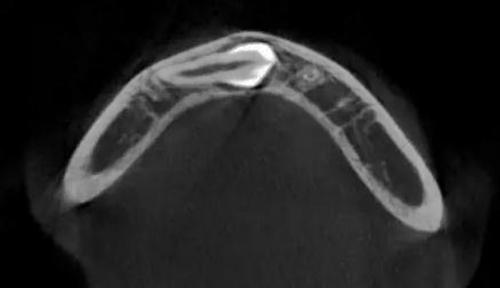

本案:患兒,女,14歲,因牙齒矯正來院,檢查見83滯留,43未見萌出,拍片發(fā)現(xiàn):43埋伏阻生于31、41、42根尖下方,按照正畸診療計(jì)劃,擬行43拔除術(shù)。

CBCT顯示